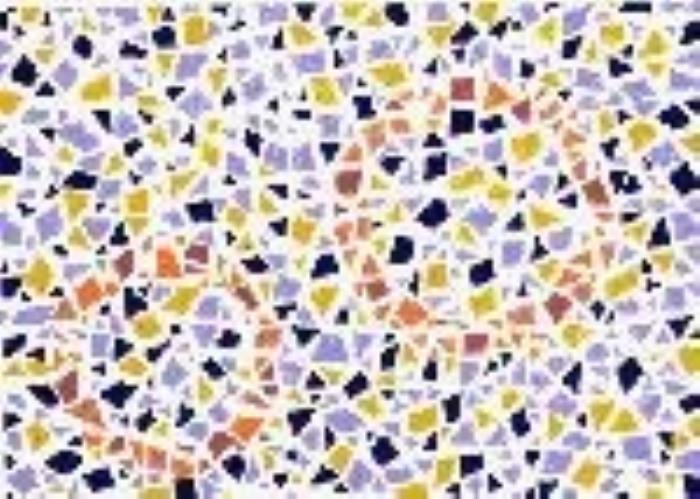

(正常 绿色盲 红色盲 蓝黄色盲)

(正常 绿色盲 红色盲 蓝黄色盲)

根据不同类型的色盲,以及色盲的严重程度,患者多少是能看到一些颜色的,或者说只是有些颜色看起来跟常人不同,但并不等于是“黑白”的世界。